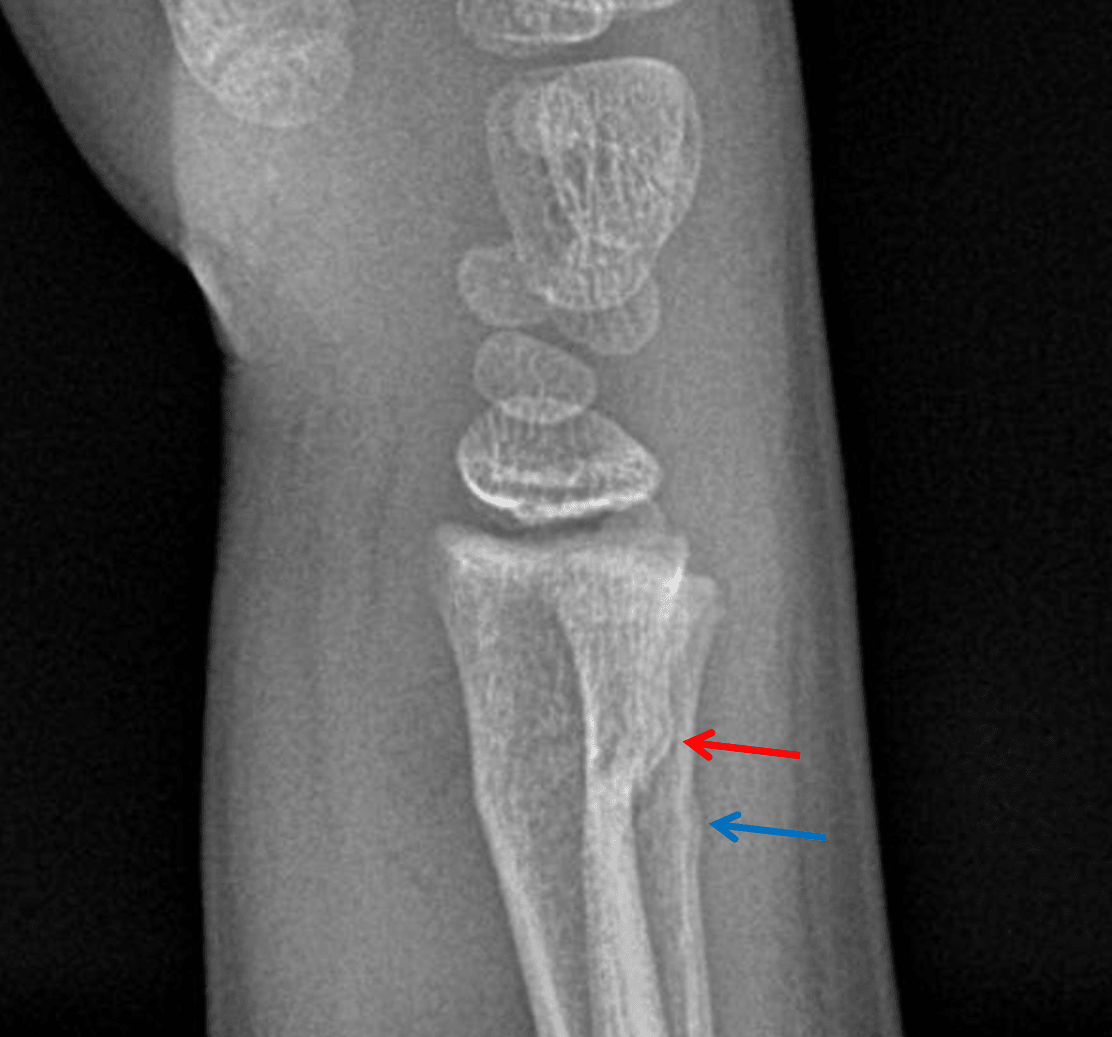

• Acute buckle fractures of the distal radial and ulnar metaphyses with slight dorsal angulation

Acute buckle fractures of the distal radial and ulnar metaphyses with slight dorsal angulation.

No joint malalignment.

Acute buckle fractures of the dorsal distal radial (red arrow) and ulnar (blue arrow) metaphyses.